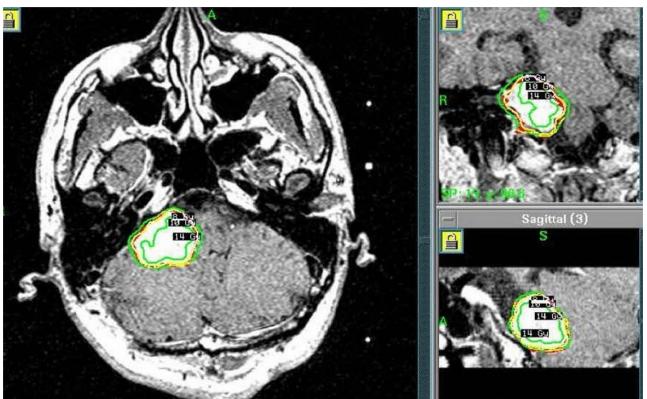

图2所示。伽玛刀放射外科治疗计划。肿瘤治疗时的边缘剂量为10Gy(50%isodose等剂量线)。

2004年5月,采取右侧乙状窦后入路切除肿瘤。术中肿瘤质地坚实(solid),血管相对丰富,易出血,部分切除肿瘤(图1A-B),于2005年8月行伽玛刀放射外科治疗(GKS)(图2)以控制当时的残留肿留。2007年5月行第二次手术切除,因蛛网膜边缘不清,与面听神经和后组颅神经粘连严重,残留部分肿瘤囊壁(图1C-D)。病人每6个月定期随访脑部MRI(图1E-I),最初的残留肿瘤的大小是稳定的。2013年11月,常规随访MRI显示肿瘤开始生长(图1J)。2014年4月出现进行性头痛、眩晕、和恶心,MRI显示肿瘤肿块增大。2014年6月(图1K-L)进行次全肿瘤切除,术中发现显示,肿瘤有两个部分,也就是说,有一部分是软的且相对容易切除,另一部分有弹性伴有纤维组织,蛛网膜边界不清楚,与面听神经和后组颅神经严重粘连。本病例的第二次及第三次手术均由同一位神经外科医生完成。